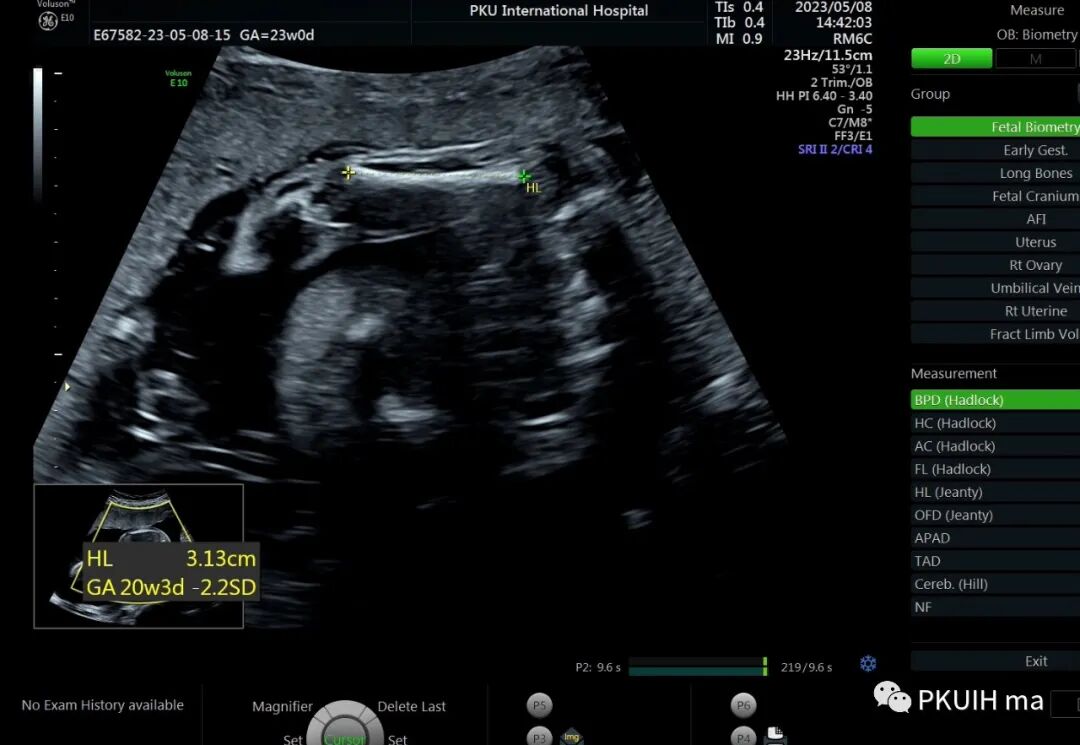

孕23周常规筛畸发现四肢长骨偏短,孕妇月经正常,核对早孕超声,孕周也没问题。

双顶径及头围正常,骨骼回声强度没有发现异常。